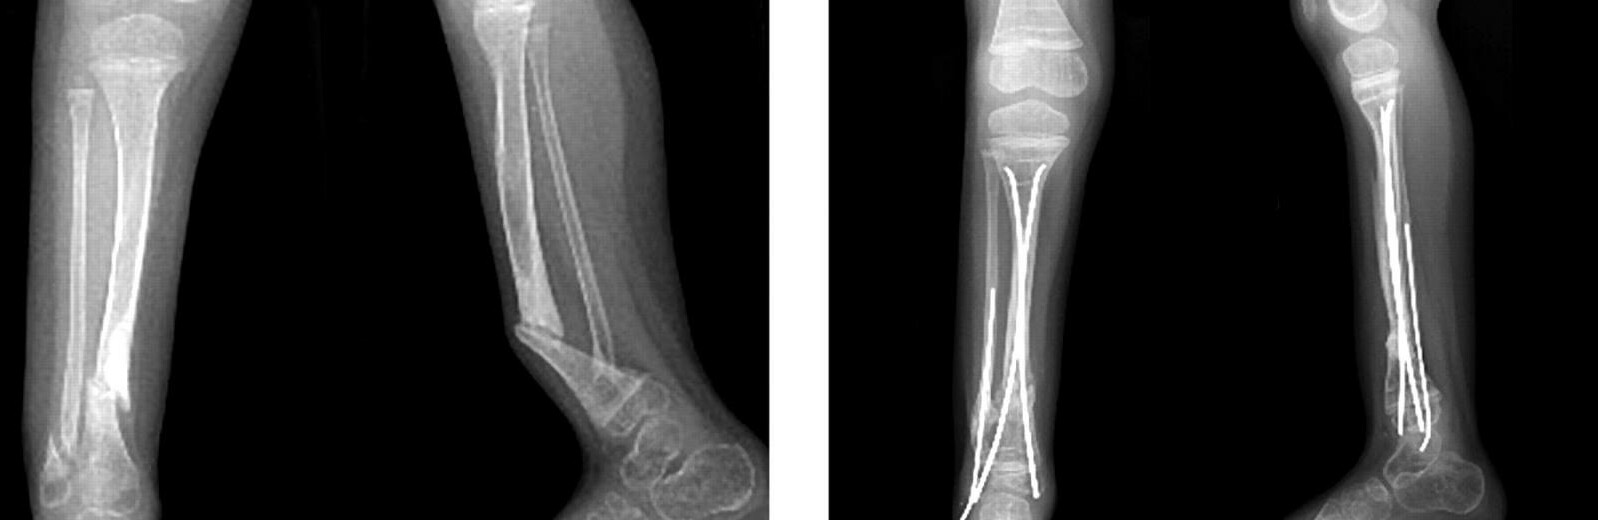

На Камчатке психически нездоровый житель поселка Палана сломал ногу семилетнему сыну за то, что ребенок плохо запоминал алфавит. Как рассказали в краевом следкоме, 39-летний мужчина схватил мальчика за руку и ногу и с силой бросил его на пол. Ребенок получил закрытый перелом большой берцовой кости.